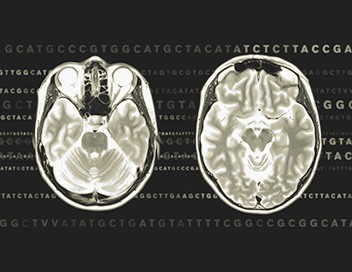

Lone Frank, journaliste danoise, justifie son caractère introverti et anxieux par une douloureuse histoire familiale. Décidée à changer de comportement, elle se soumet à divers tests et rencontre psychologues et généticiens. Elle cherche à savoir si la vie d'un individu est déterminée dès la naissance. Si le matériel génétique supplante le rôle de l'éducation sur le comportement. Ce documentaire permet de constater que ce ne sont pas les gènes ou les traumatismes de l'enfance seuls qui déterminent le développement, mais l'interaction entre patrimoine génétique et environnement. Par exemple, la façon dont chacun mène sa vie détermine l'activation ou non de certains gènes.